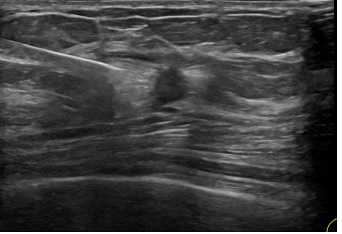

상기환자는  외부검사이상소견 조직검사위해 내원하신 50대중반

여성분으로 의심스러운 좌측혹 조직검사 시행해 유방암 진단되었습니다